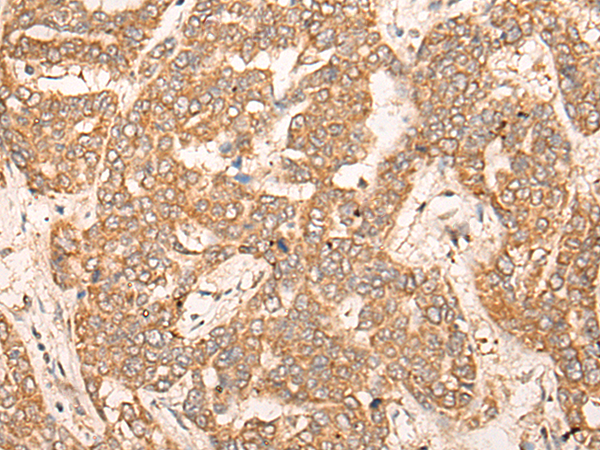

IHC positive control: |

Human liver cancer |